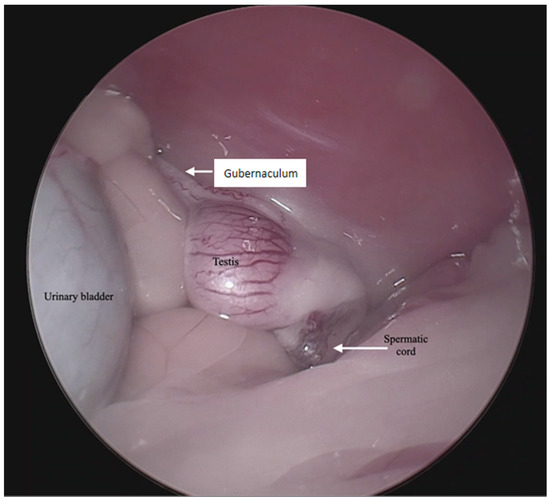

Figure 2.

Endoscopic image of the anatomical structures in the intra-abdominal testis.

For the surgical procedure, in all cases, inhaled anesthesia was used, and anesthesia monitoring was performed by qualified personnel. In all cases, the main trocar was placed just caudal to the umbilicus using a Hasson technique in 10 cats, modified-Hansson in six cats, and the Veress needle technique in three cats. A small skin incision (<10 mm) was made at this site, and subcutaneous tissues were dissected to visualize the external rectus abdominis sheath; a small stab incision was made into the peritoneal cavity. In 16 cats, a 5 mm trocar was inserted through the incision, and a 6 mm trocar into the remaining 3 cats. The capnoperitoneum was achieved at a rate of 1–2 L/min to an intrabdominal pressure of 7–9 mmHg. A rigid 5 mm telescope with 0° or 30° angle vision was inserted through the trocar, and the abdomen was explored systematically. When an abdominally retained testes was detected, a second access port with a 5 or 6 mm trocar was inserted in a caudal position and slightly lateral to the retained testis, and particularly in the case of the three bilaterally cryptorchid cats, the second trocar was inserted in the center of the caudal abdomen. The second trocar placement was performed with the use of direct visualization through the laparoscope, and transillumination of the abdominal wall was used to avoid blood vessels. To be able to work with two trocars, external suture was used to suspend the testis. The size of the needle was dependent on the size of the animal but had a curvature and sufficient length to allow comfortable entry and exit through the abdominal wall. In the current clinical cases, a 3/8 circle reverse cutting needle ranging from 24 to 30 mm length was commonly used. With transillumination, the most appropriate place to insert the needle was located, avoiding vascularized areas. First, the needle was passed through the abdominal wall, under direct endoscopic visualization and then passed through the testis carefully avoiding vascular structures, and ultimately pulling the needle out through the abdominal wall again. The suture was secured externally with the help of a hemostat, thus fixing the testis to the abdominal wall. In three cases, a percutaneous grasping technique was performed using an open-loop grasper that allowed the testis to be fixed to the abdominal wall with a single puncture; and in three cases, a third port was implemented with two paramedian trocars. With these maneuvers, the detailed visualization of the vascular pedicle, the spermatic cord, and the gubernaculum was achieved (Figure 1 and Figure 2).